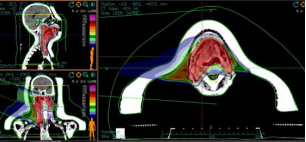

In January 2024, the patient noticed pain, ulceration, and a localized mass on the right side of the tongue, accompanied by local pain, swelling, surface ulceration, and fluid discharge. The tumor gradually increased in size. On July 18, 2024, a biopsy of the tongue mass was performed, with pathological results indicating moderately differentiated squamous cell carcinoma of the right side of the tongue. Maxillofacial and neck MRI revealed a mass in the tongue and right tongue base with abnormal enhancement, likely invasion of the adjacent soft palate, orbicularis oris muscle, and right epiglottis, with narrowing of the laryngopharyngeal cavity at the same level. Enlarged lymph nodes in the right cervical vascular space were observed, suggesting metastasis. The patient was definitively diagnosed with squamous cell carcinoma of the tongue, cT4aN2bM1, stage IVC. After comprehensive evaluation of the condition and clinical staging, carbon ion therapy was initiated on July 30, 2024, with nutritional support. The treatment plan included GTV: 64Gy (RBE)/17Fx, CTV1: 60Gy (RBE)/15Fx, and CTV2: 56Gy (RBE)/14Fx. The entire treatment was successfully completed.

Figure 1. Carbon ion therapy plan: GTV: 64Gy (RBE)/17Fx, CTV1: 60Gy (RBE)/15Fx, CTV2: 56Gy (RBE)/14Fx.